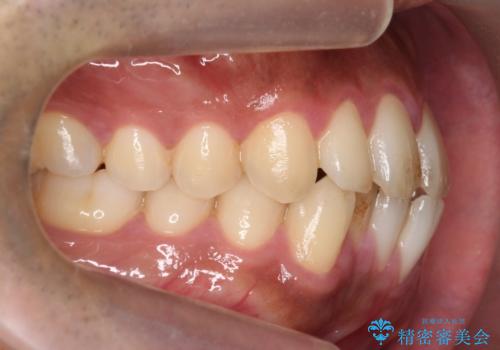

前歯が反対にかんでいる 部分ワイヤーとインビザラインの併用で短期治療

- 前歯の並びを気にして来院。

前歯が一本奥に入っているのを乗り越えるにはワイヤー矯正が治療期間も短く、歯に負担が少なく有利と説明しました。

上はワイヤー部分矯正、下はインビザラインの部分矯正コースを行いました。